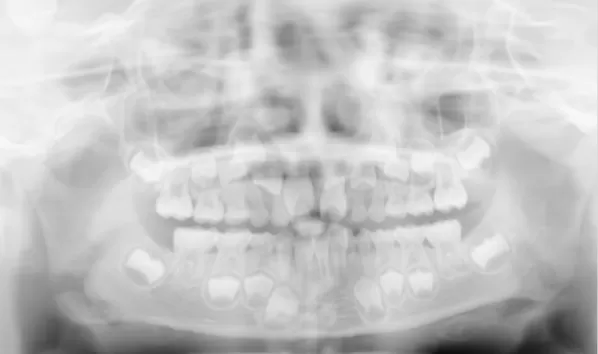

Rayons X avant le traitement

[Radiographie panoramique/Céphalogramme latéral]